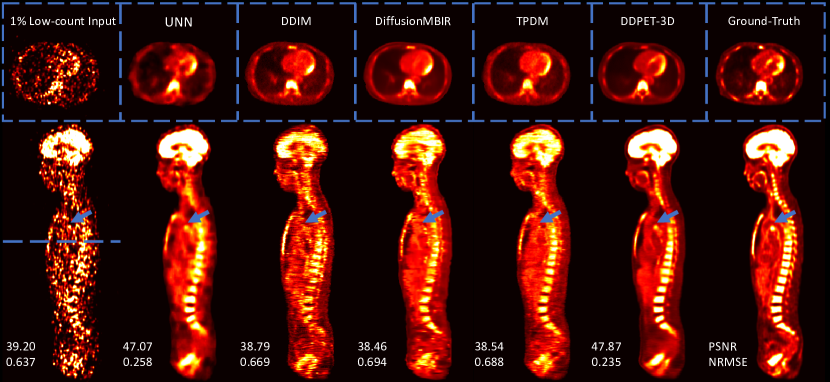

The proposed DDPET-3D was compared with UNN [19], DiffusionMBIR [32], and TPDM [33]. As described previously, UNN was chosen because it was also proposed to achieve noise-aware denoising and was one of the winning method in 2022 Ultra Low-dose PET Imaging Challenge. DiffusionMBIR and TPDM were selected because they were recent works proposed to address the diffusion 3D inconsistencies problem in medical imaging. We also compared with the standard DDIM (Denoising Diffusion Implicit Models) sampling [36]. Detailed implementations of different methods will be provided later in this paper (see Methods).

As presented in Fig. 8, standard DDIM sampling produced images with severe inconsistencies between slices in the sagittal view. Both DiffusionMBIR and TPMD improved the results, but the problem still exist. Proposed DDPET-3D method produced noticeably more consistent reconstructions. Moreover, even though other diffusion models produced visually realistic PET images, they failed to accurately reconstruct the structure of different organs. For example, all other diffusion models produced images with distorted myocardium as shown in the transverse slice in Fig. 8. The proposed DDPET-3D method also recovered some fine details in the images, such as the hot spot pointed by the blue arrows in Fig. 8, which is either over-smoothed (in UNN) or barely visible (in other diffusion methods).

Another major issue of the diffusion model is inaccurate image quantification. Note that all the presented images were already normalized by the total injected activities. As shown in Fig. 8, the tracer activities in certain organs are completely wrong in other existing diffusion models. For example, the activities in the brain are noticeably lower in DDIM, DiffusionMBIR, and TPDM results; the myocardium is distorted in competing baseline methods. Such differences may affect certain diagnostic tasks such as lesion detection [5]. Even though UNN produced over-smoothed reconstructions, it does not alter the overall tracer activities in different organs. Using UNN output as denoised prior (see details in Methods), the proposed DDPET-3D maintained overall image quantification. Also, using UNN as a denoised prior allows the proposed method to recover some subtle features that are almost invisible in the low-count input (blue arrows in Fig. 8).

Images were quantitatively evaluated using SSIM (Structural Similarity Index), PSNR (Peak signal-to-noise ratio), and RMSE (Root-mean-square error). To facilitate the testing process, we tested all the comparison methods using 20 patients from the entire testing dataset. There were 6 different low-count levels of all the patients, resulting in a total of 120 testing studies. Quantitative results are presented in Table II.